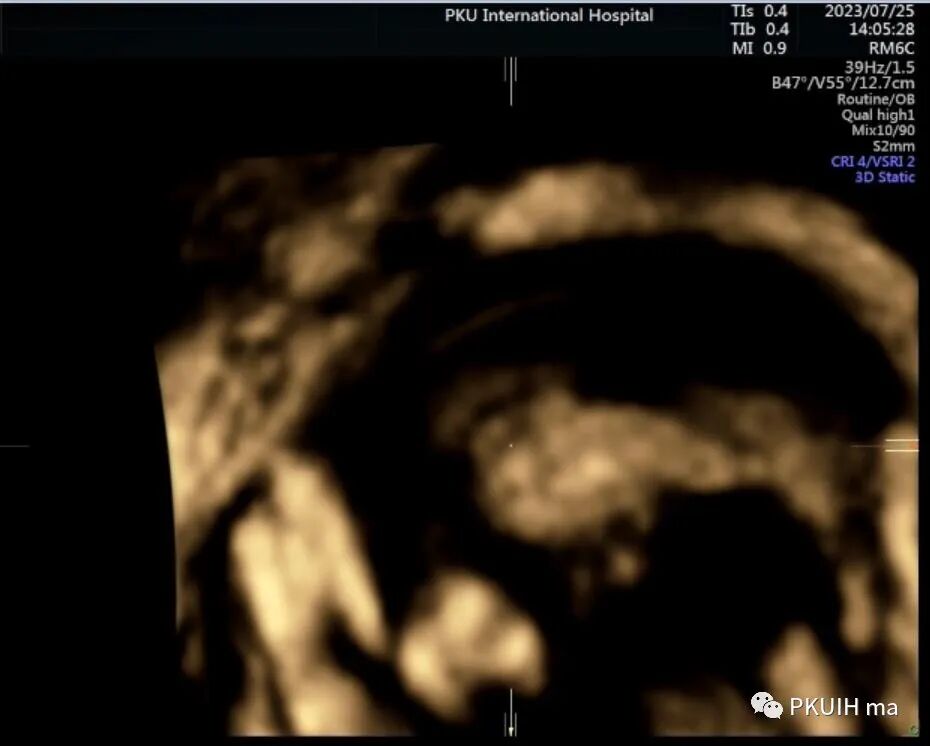

由于胎儿体位不好想着做一个三维,结果图像也不满意,只能等待胎儿仰卧或者俯卧观察正中矢状面了。

等了很久终于能打到一个矢状面的图像了,感觉胼胝体存在,长度还行,胼周动脉也有。由于孕妇太胖了怎么也打不好完整的胼胝体决定改天再观察。